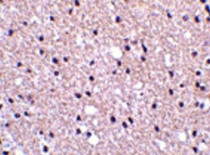

ARG46400 anti-Presenilin 1 / PS1 (CTF) antibody IHC-P image

Immunohistochemistry: Human brain stained with ARG46400 anti-Presenilin 1 / PS1 (CTF) antibody.